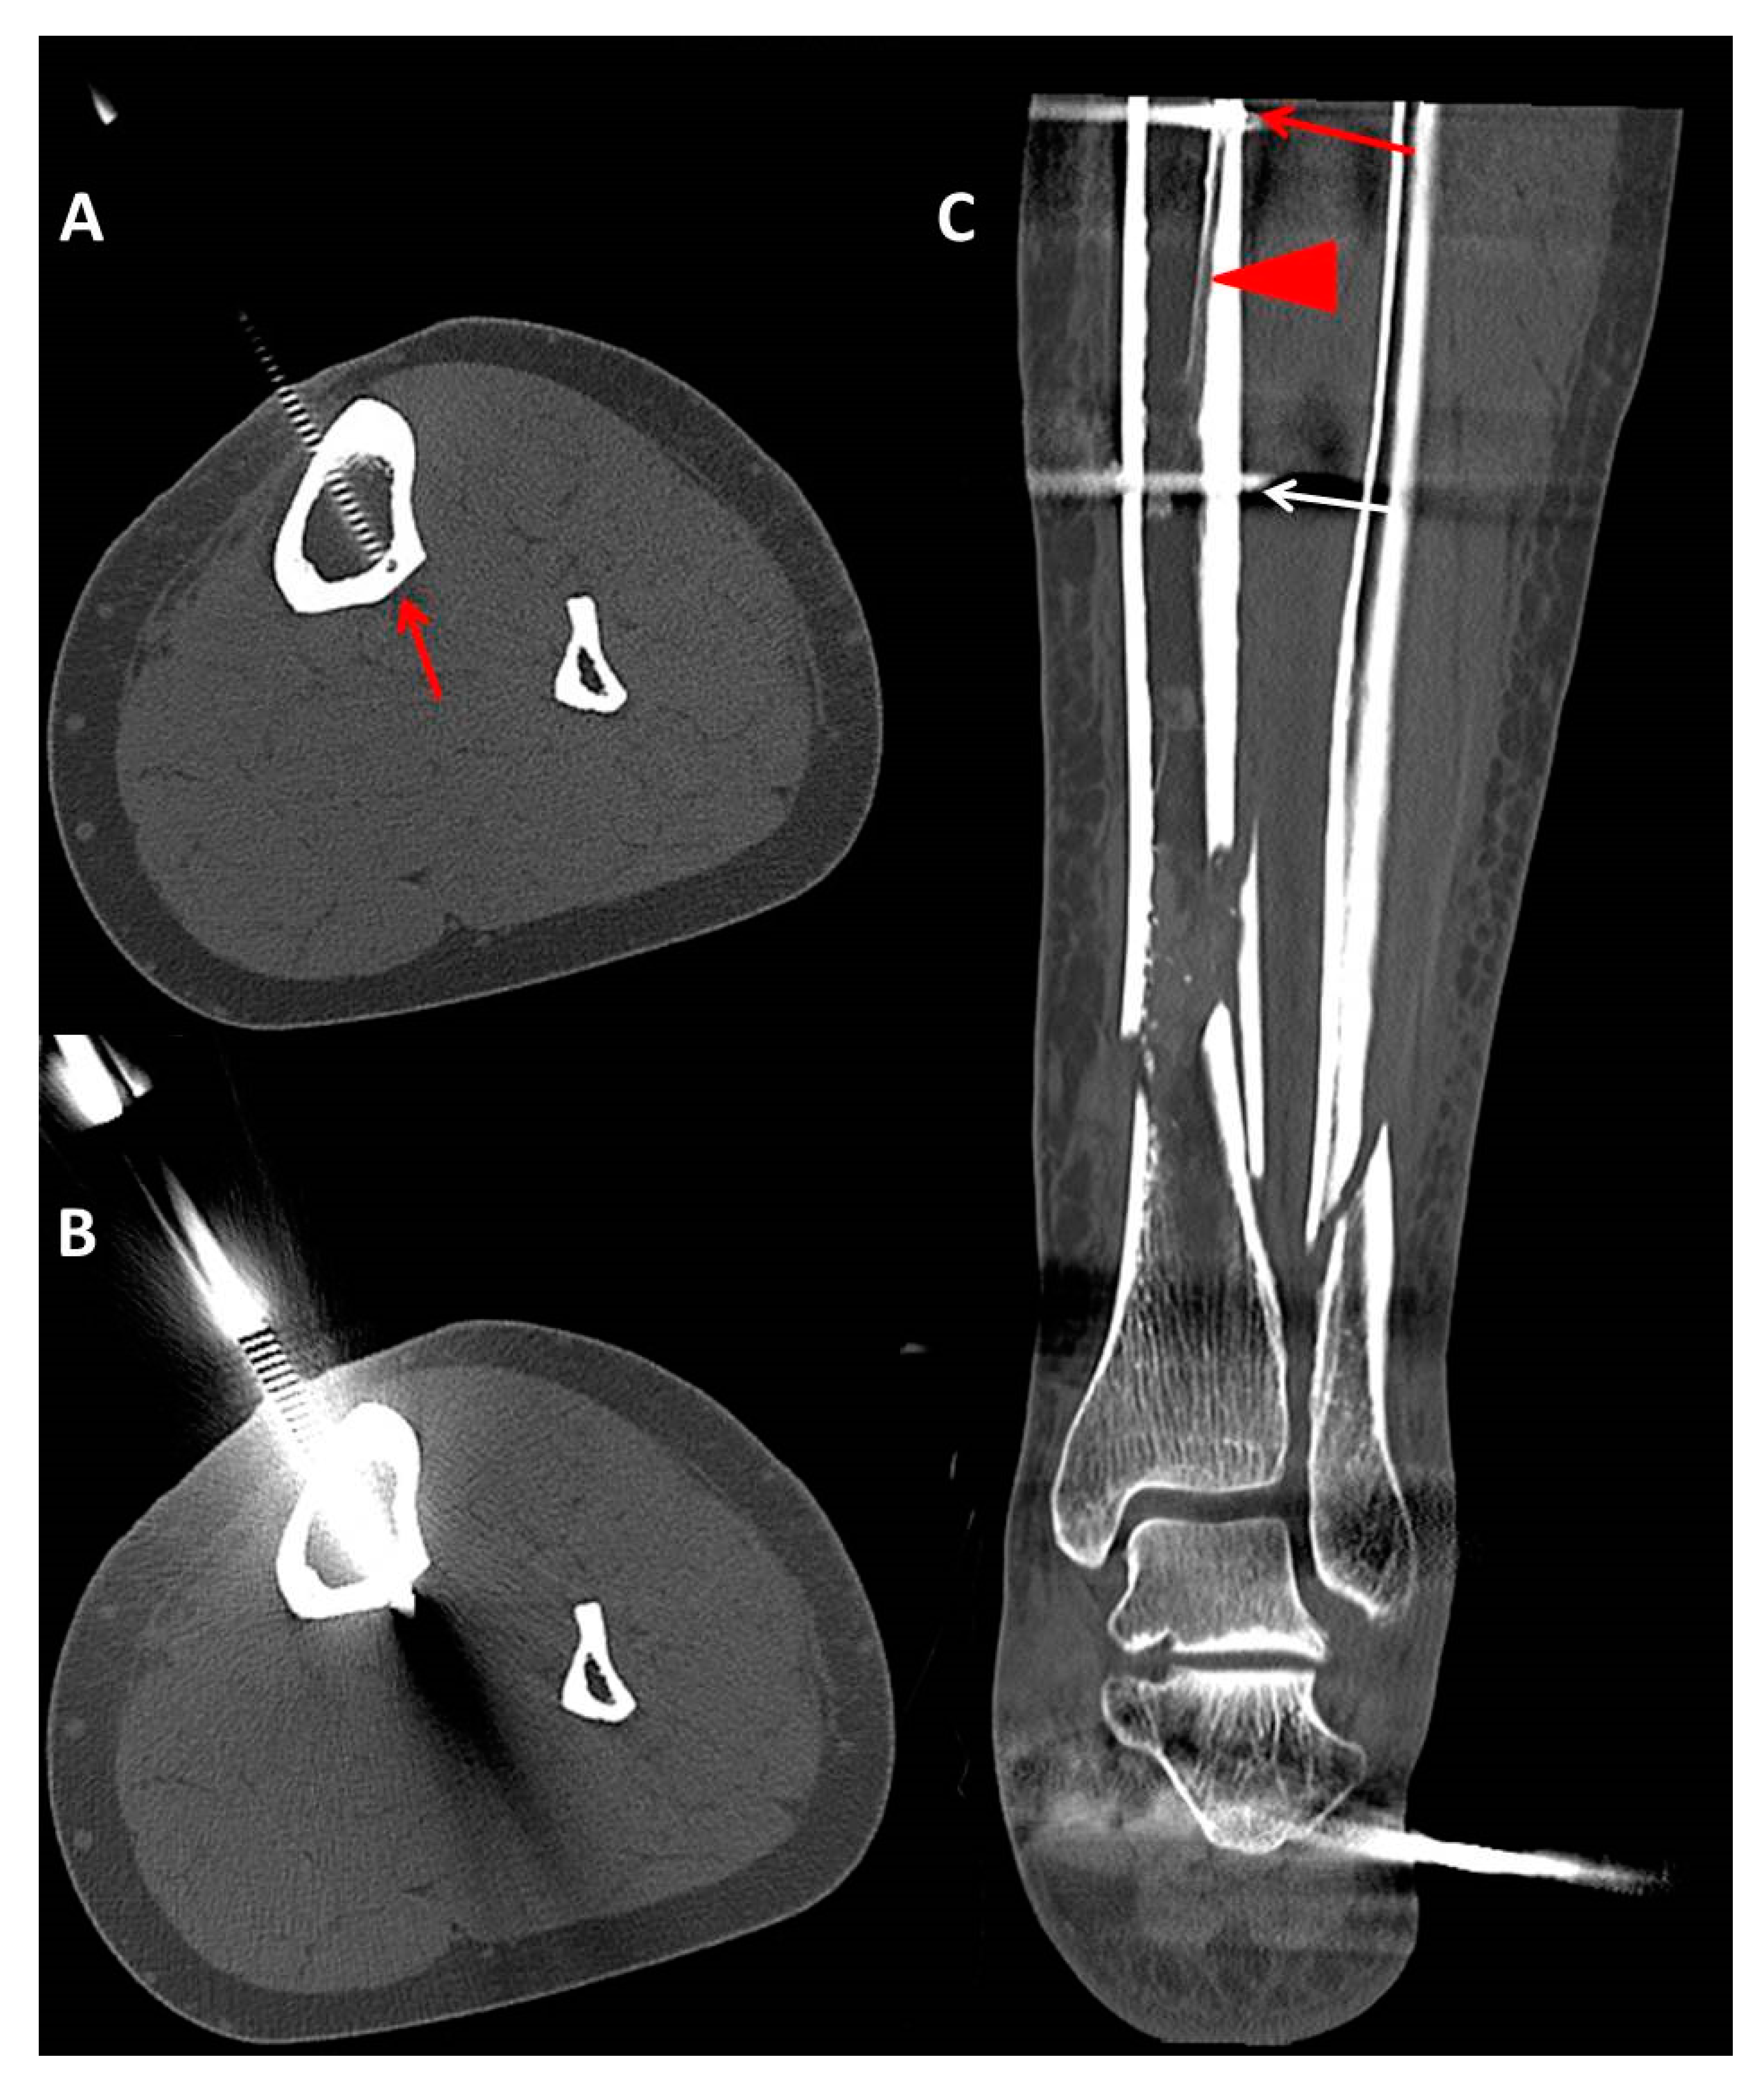

- Pin characteristics (orientation of pin application: anteromedial/tibial crest, anterolateral) and cortical position of the pins (bicortical/monocortical/transcortical) (Figure 2).

- The anatomic relationship between the TNAC and external fixation pin (topography above/below and at the level of the TNA canal, and distance between the pin and medial tibial plateau and/or the medial malleolus) for different fixation and fracture types.